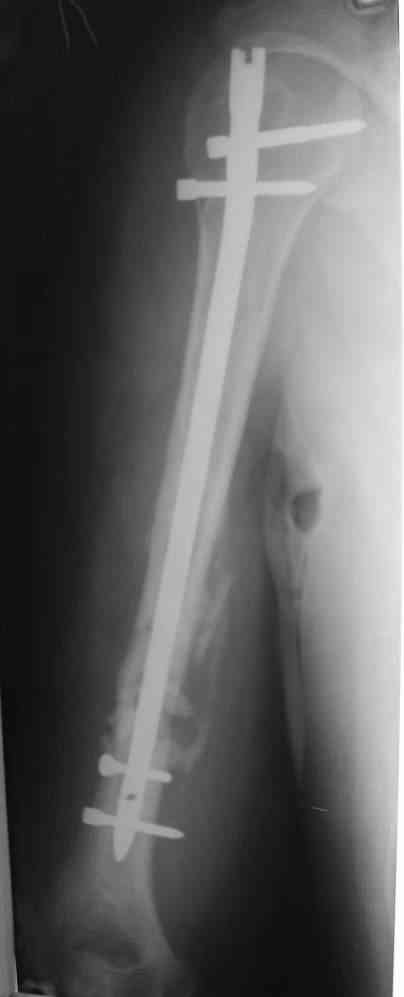

На мой взгляд, целесообразно выполнить антеградный блокируемый интрамедуллярный остеосинтез. При наличии достаточного диаметра костномозгового канала по проводнику произвести его рассверливание и установить штифт по-возможности без вскрытия места перелома. При наличии симптомов повреждения лучевого нерва необходимо выполнить его ревизию и мобилизовать отломки "открыто".

Предложение коллеги Мамонова, возможно, более привлекательно. У пациентов с невысокими функциональными потребностями есть смысл добиваться не сращения, а стабильной, безболезненной и функциональной конечности, что может быть достигнуто "эндопротезированием диафиза" интрамедуллярным стержнем. У нас несколько таких больных наблюдаются уже 2-3 года, вроде неплохо.

Будут трудности с закрытым вскрытием канала (нужен инструмент типа длинного шила). Можно взять штифт с блокированием, а можно и прямоуголного сечения типа Зверева-Ключевского. Есть варианты закрытого штифтования в нейтральном положении, с компрессией, открыто с резекцией и компрессией.

Штифт - отвисание проксимального отдела - накостный остеосинтез, нагноение, АФВ с ревизиями раны, опять пластина и снова нестабильность. Была удалена пластина и выполнен БИОС штифтом ChM (ДЕОСТ). Через 2 нед. пациент сел за руль и вышел на работу. Причем так и работает до сих пор уже 1,5 года, хотя полного сращения мы вроде бы не достигли ( снимки пришлю позже) - пациент не приходил на осмотры, общался только по телефону.